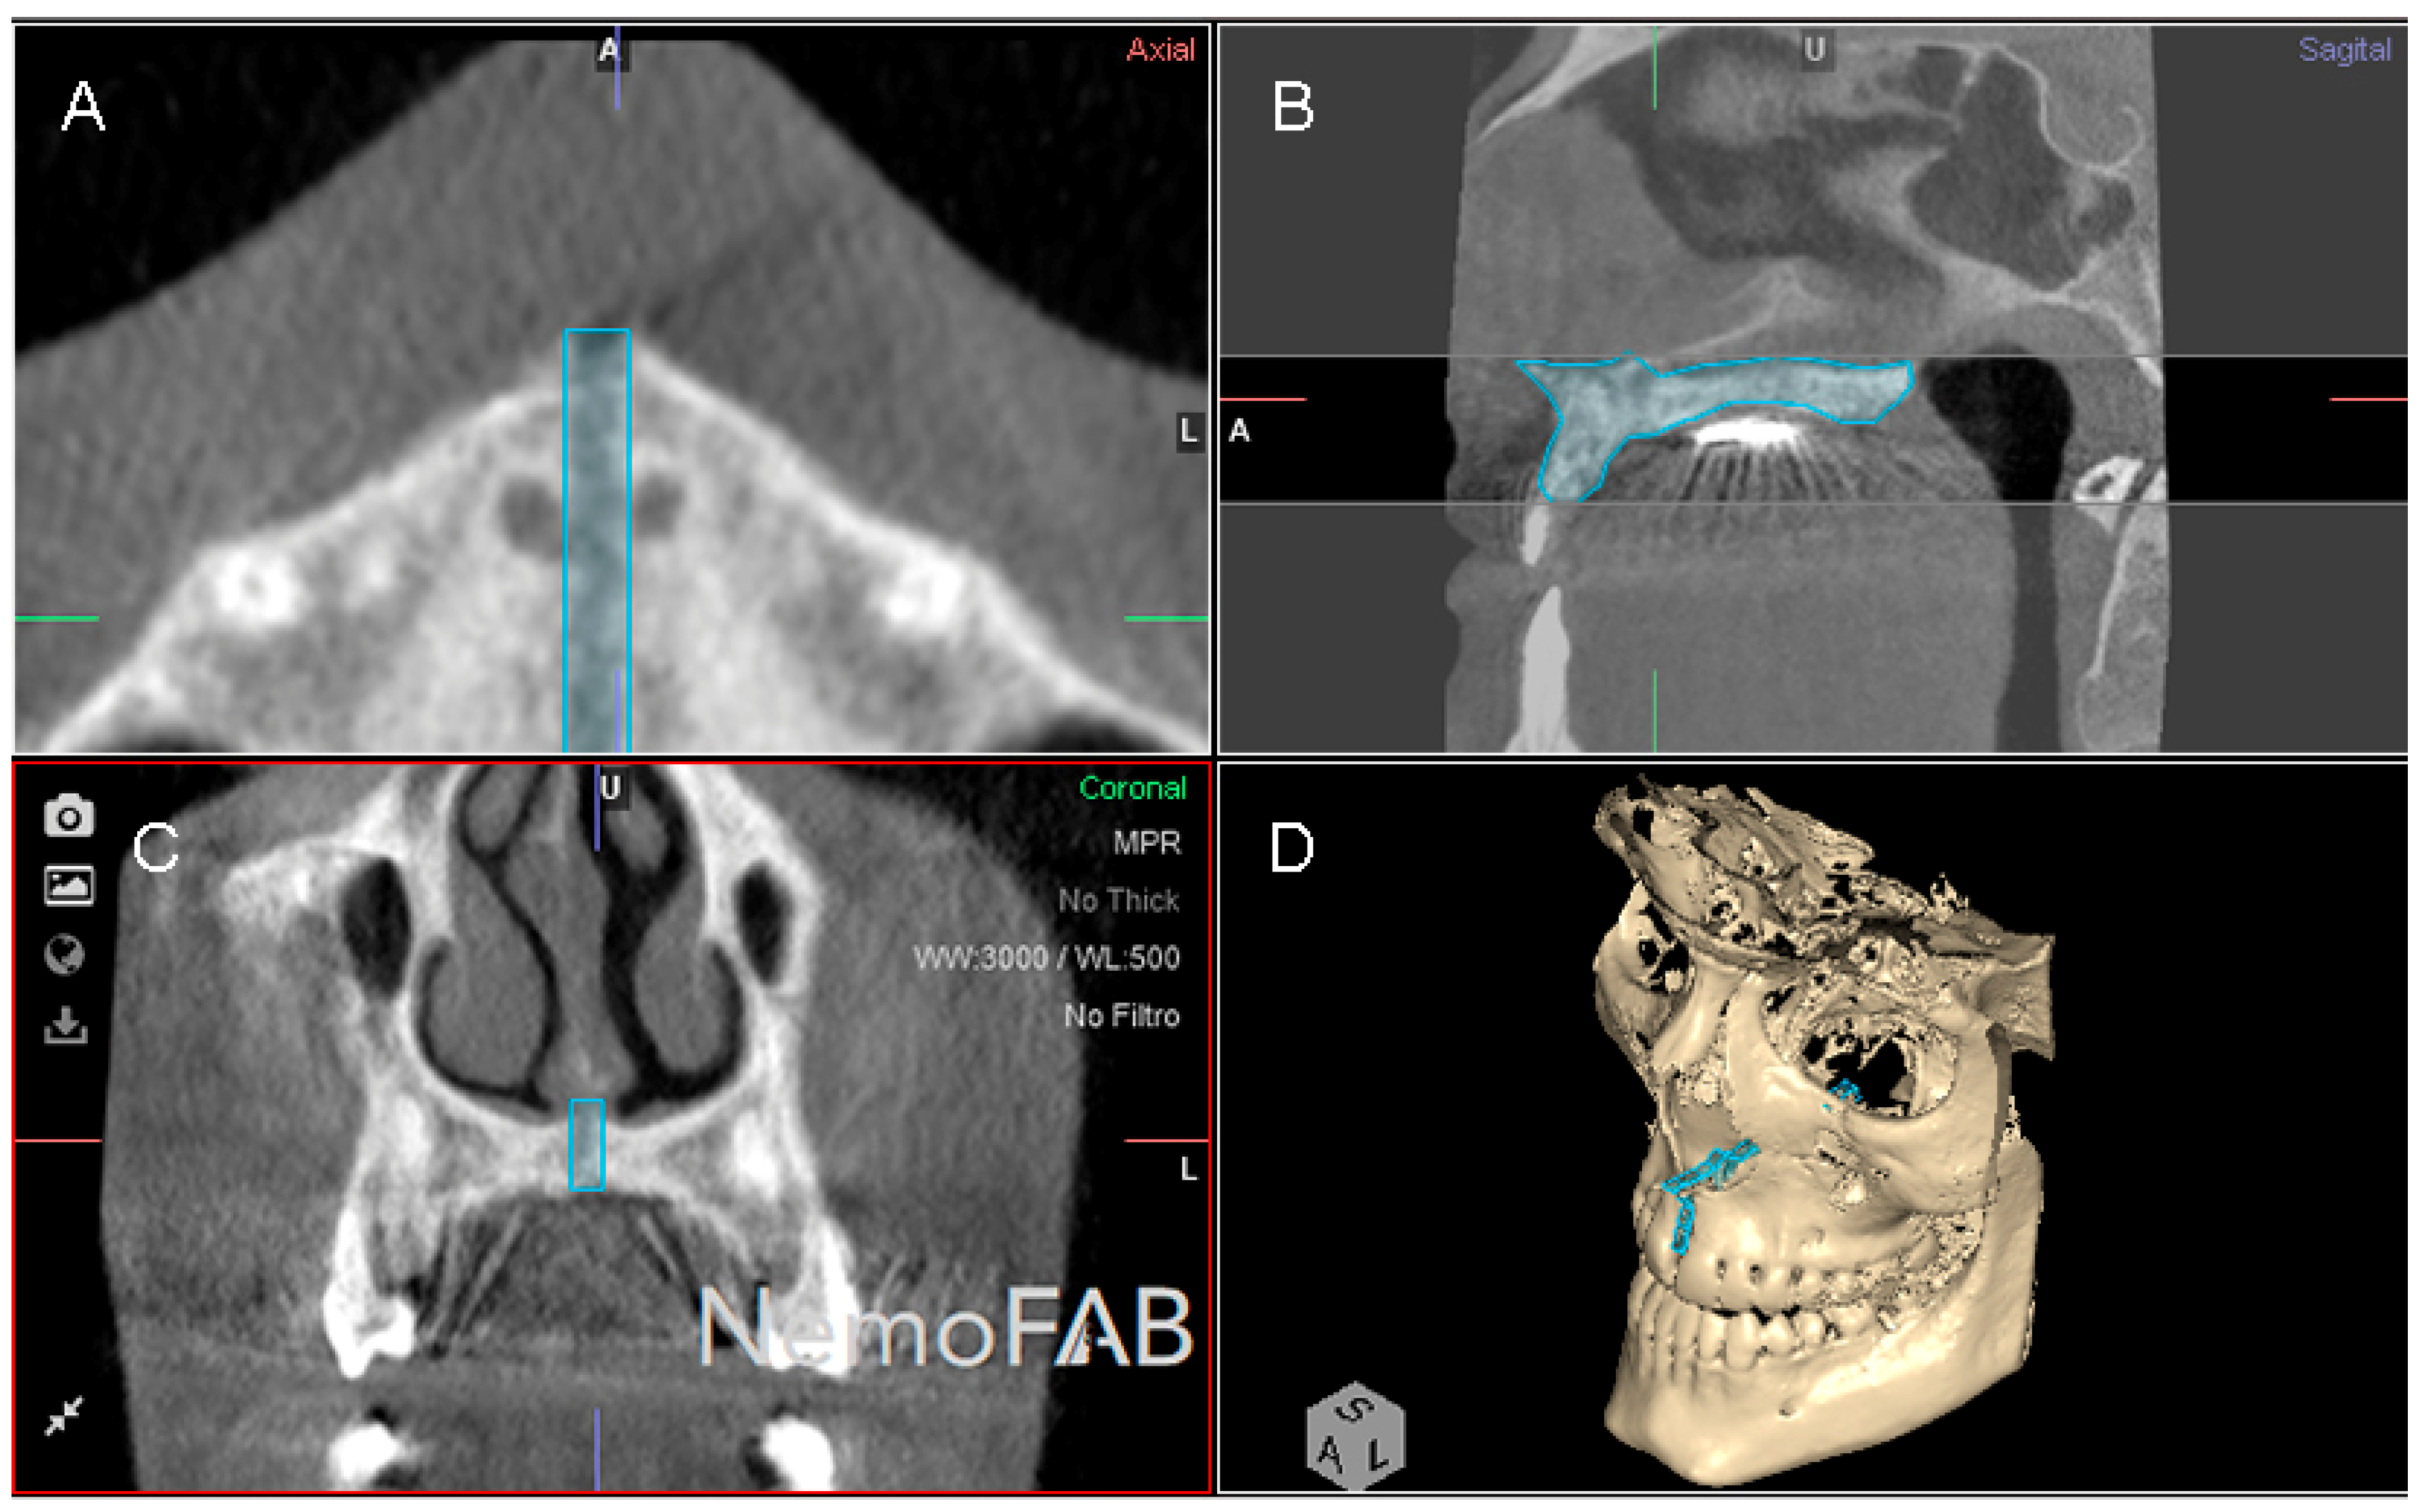

Then, the geometric prism of the expanded palatine suture was selected and isolated by analyzing the boundaries of the palatine suture expansion in transversal (Figure 3A), sagittal (Figure 3B), coronal (Figure 3C) plane and the three-dimensional reconstruction of the CBCT scan (WhiteFox, Satelec, Merignac, France) (Figure 3D). Subsequently, the anatomical references that delimited the boundaries of the geometric prism after the palatine suture expansion were identified by the two anterior nasal spines and the two posterior nasal spines.

Figure 3.

(A) Boundaries of the palatine suture (blue line) after the RME procedure through McNamara appliance was performed, at transversal plane, (B) sagittal plane, (C) coronal plane and (D) at three-dimensional reconstruction of the CBCT scan.